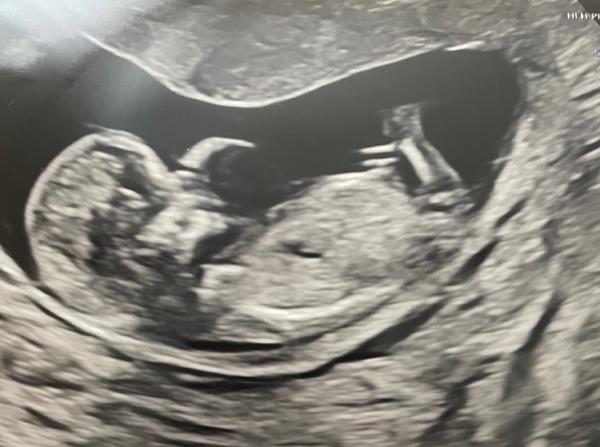

chtěla bych se zeptat, zda-li byste odhadl pohlaví miminka z fotek, které jsou z prvního screeningu ve 13. tt.

z fotografie to jednoznačné není. Jednak je spolehlivost odhadu ve 13. týdnu malá a také statický snímek nedokáže nahradit vyšetření v reálném čase.